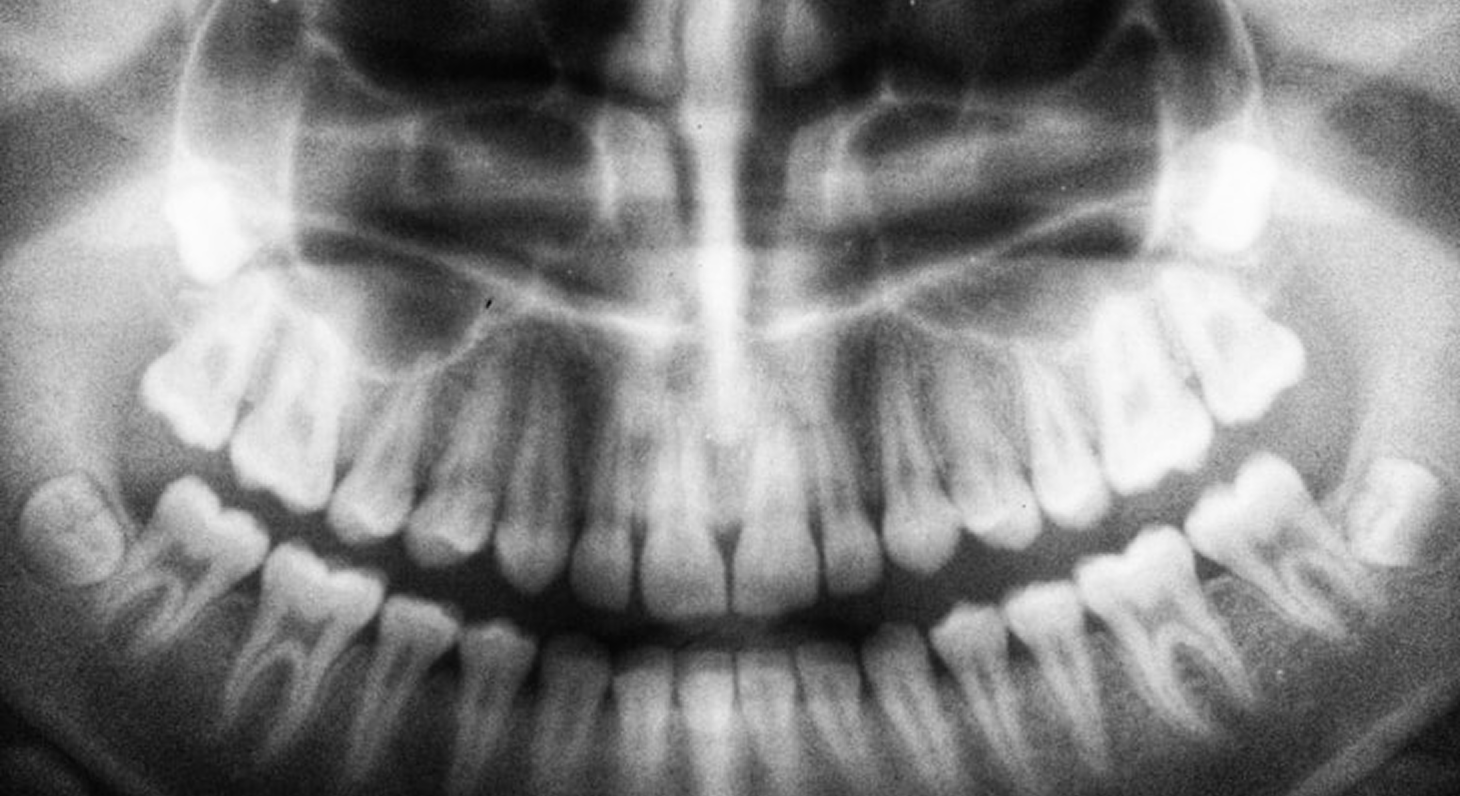

OPG offers a panoramic view of the upper and lower jaws in one scan. It’s commonly used for assessing impacted teeth, bone levels, cysts, and overall oral health. With digital advancements, OPG scans now deliver safer, faster, and clearer results.